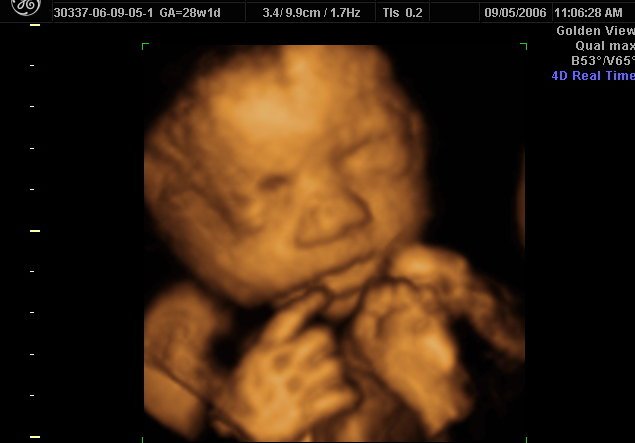

Kliniky v posledných rokoch používali 2D ultrazvuky, ktoré boli schopné ukázať klientom bijúce srdcia nenarodených detí. S príchodom 4D, budú však môcť ukázať ženám obrázok ich dieťaťa v ich životnej podobe. Technologický pokrok 4D je taký dramatický, že tieto snímky ukazujú záhadnú podobnosť k dieťaťu po jeho narodení.

Vďaka novej technológii ultrazvuku sa zvýšil počet žien, ktoré sa rozhodli pre život dieťaťa radšej než pre potrat. A to zo 14% na 74%. Tvrdí to zakladateľka a riaditeľka kliniky Kathleen Eatonová.